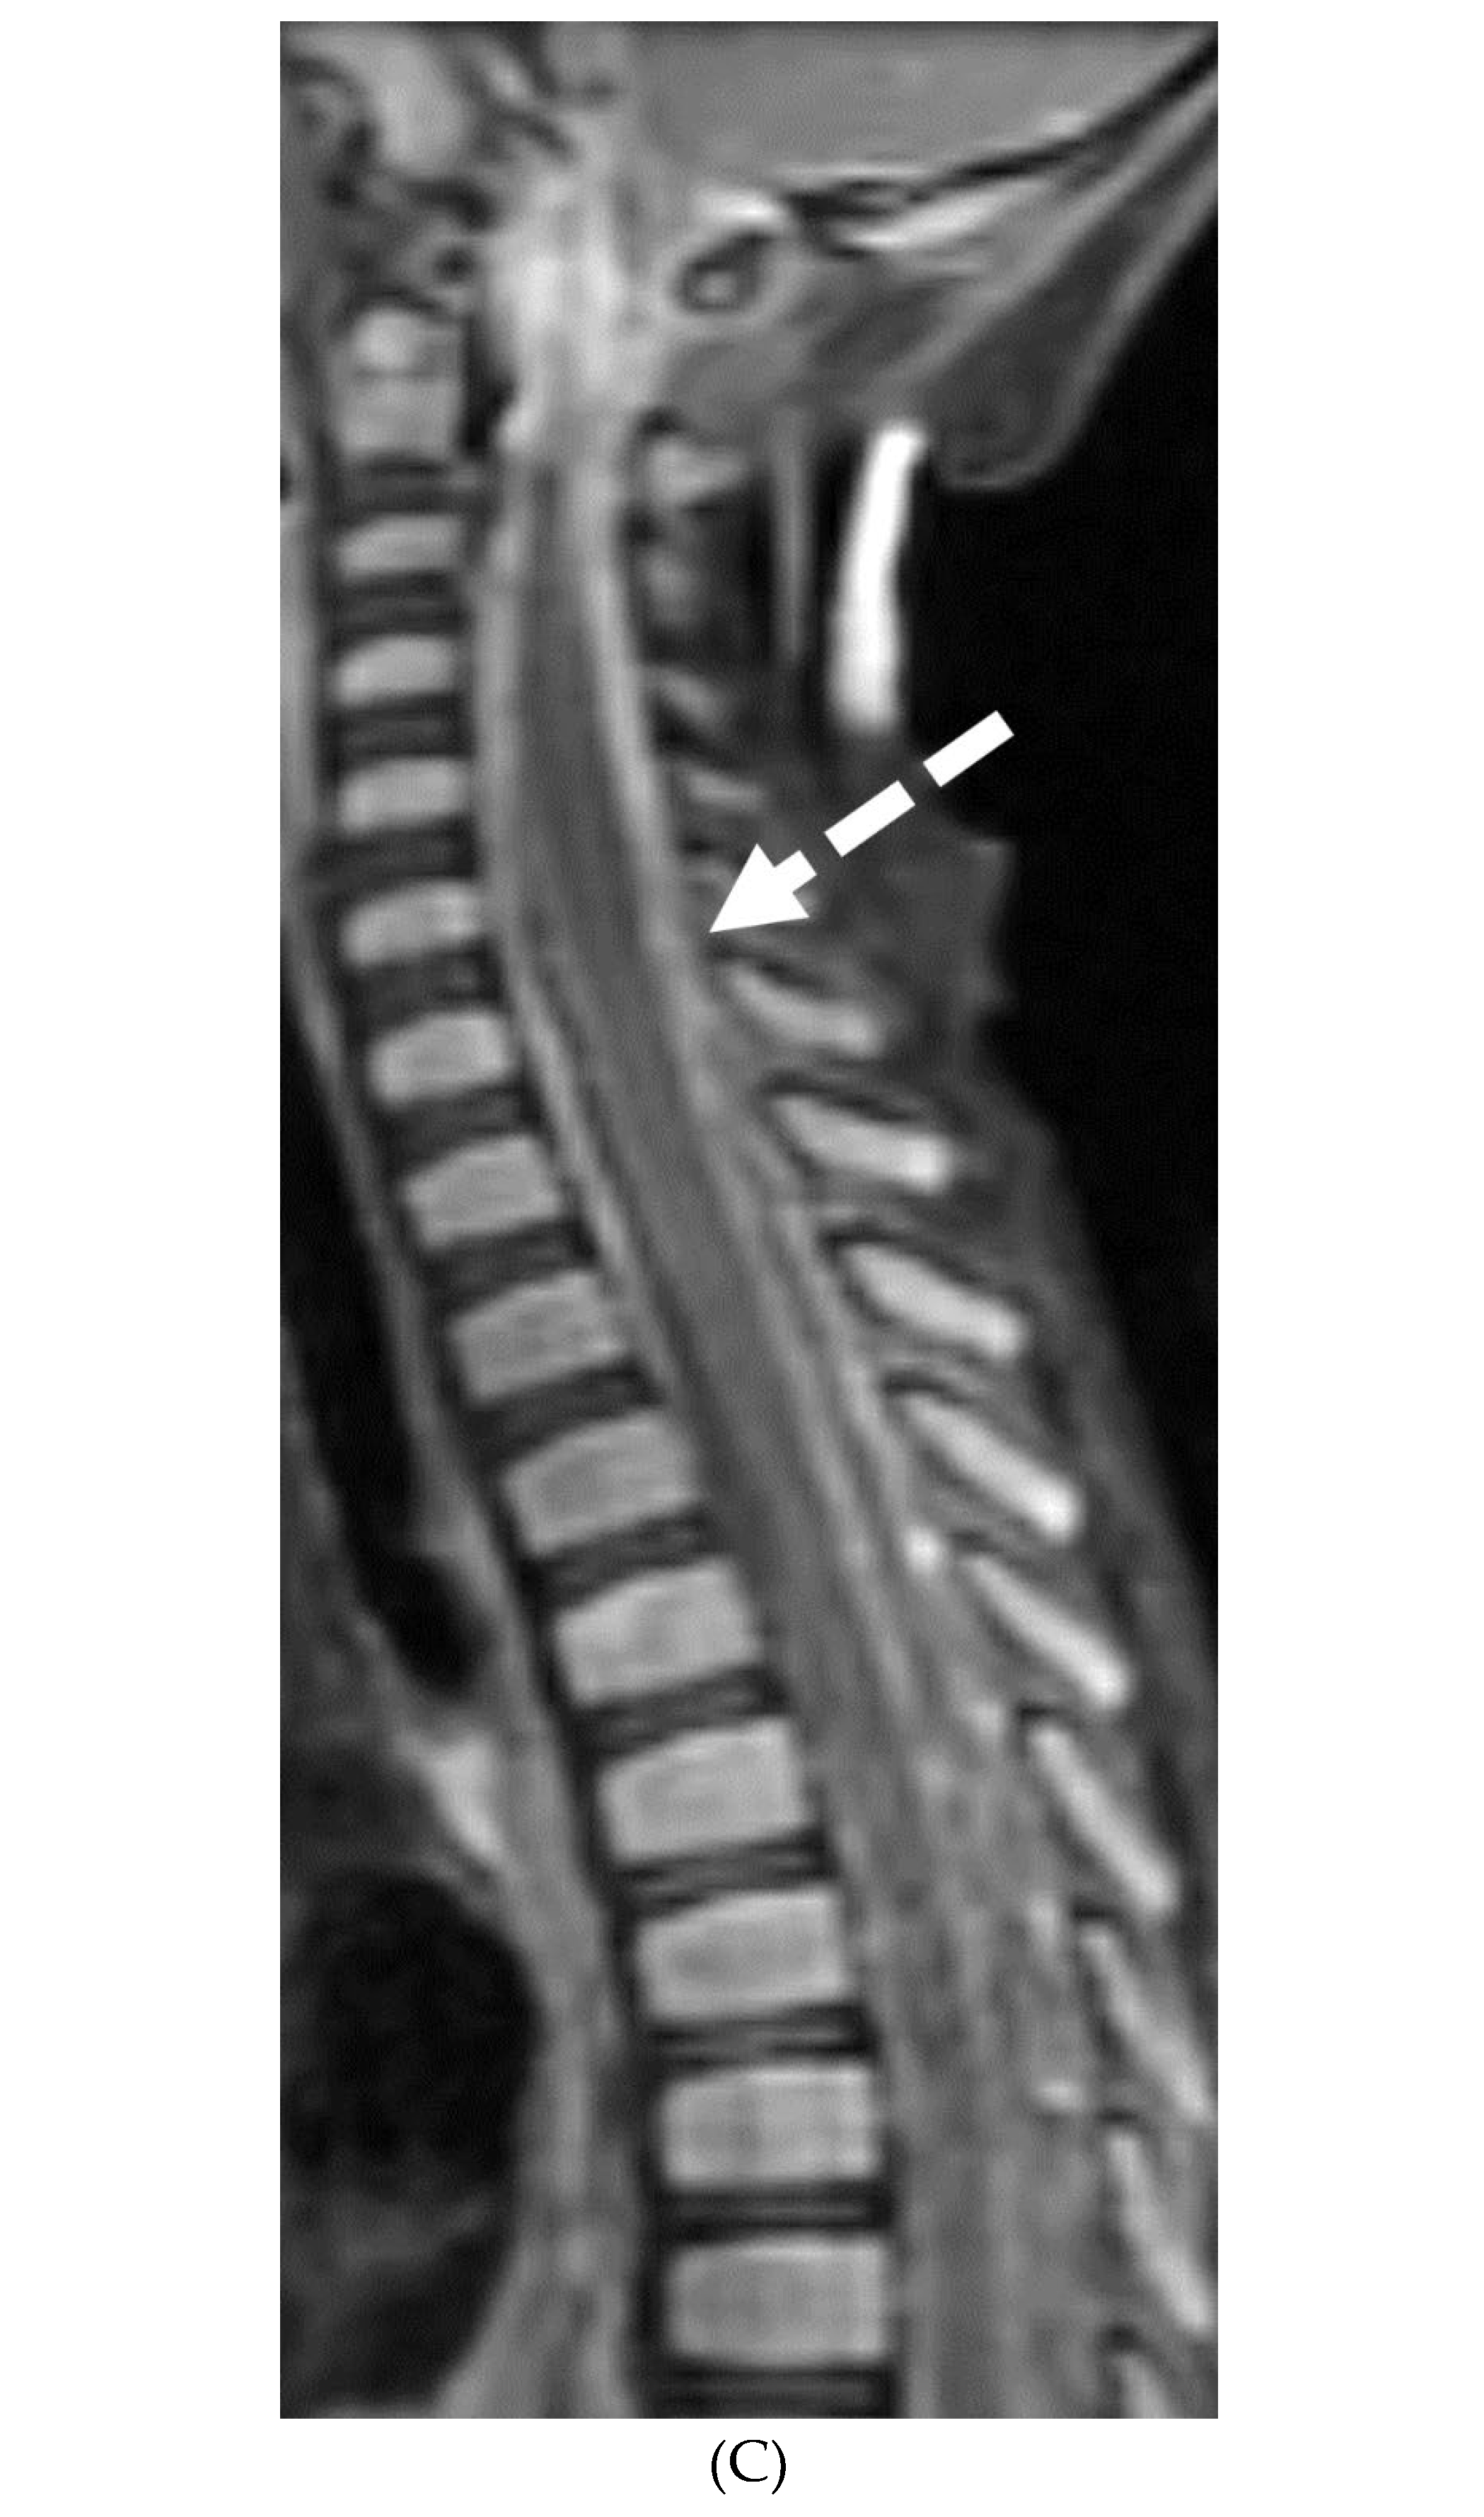

PRIMARY BRAIN TUMOR LEPTOMENINGEAL METASTASES

- Kralik SF, O'Neill DP, Kamer AP, Rodriguez E, Ho CY. Radiological diagnosis of drop metastases from paediatric brain tumours using combination of 2D and 3D MRI sequences. Clin Radiol. 2017 Oct;72(10):902.e13-902.e19. Epub 2017 May 22. PMID: 28545686. [CrossRef]

- Silva, F.A.B., Senerchia, A.A., Cappellano, A. et al. Medulloblastoma and Drop Metastasis: MRI Evaluation and Optimized Protocol. Curr Radiol Rep 3, 26 (2015). [CrossRef]

- Harrison SK, Ditchfield MR, Waters K. Correlation of MRI and CSF cytology in the diagnosis of medulloblastoma spinal metastases. Pediatr Radiol. 1998 Aug;28(8):571-4. PMID: 9716623. [CrossRef]

- Singh SK, Leeds NE, Ginsberg LE. MR imaging of leptomeningeal metastases: comparison of three sequences. AJNR Am J Neuroradiol. 2002 May;23(5):817-21. PMID: 12006284; PMCID: PMC7974747.

- Porto L, Kieslich M, Bartels M, Schwabe D, Zanella FE, Du Mesnil R. Leptomeningeal metastases in pediatrics: magnetic resonance image manifestations and correlation with cerebral spinal fluid cytology. Pediatr Int. 2010 Aug;52(4):541-6. PMID: 20534022. [CrossRef]